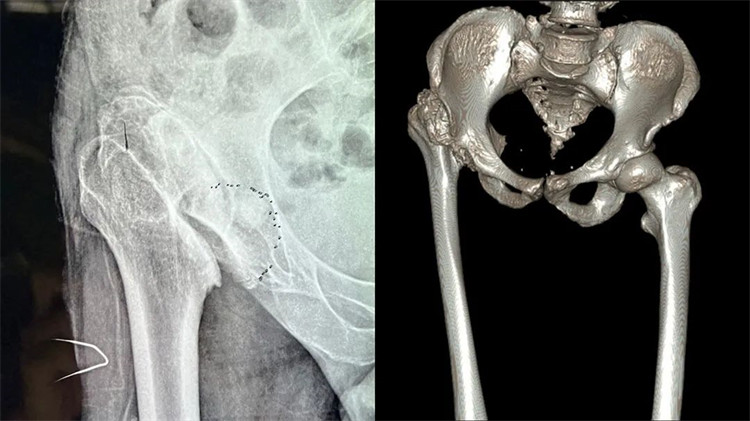

患者術(shù)前嚴(yán)重變形的髖關(guān)節(jié)

周大伯來院后經(jīng)X線片及CT檢查,發(fā)現(xiàn)右側(cè)股骨頭壞死、形態(tài)失常,已經(jīng)完全脫離正常的位置,且很難找到真臼,右側(cè)髖臼形態(tài)失常、部分骨質(zhì)缺失。想要徹底解決周大伯的問題,需要進(jìn)行右側(cè)人工全髖關(guān)節(jié)置換。但周大伯患病50余年,且有過失敗的手術(shù)病史,髖關(guān)節(jié)感染后遺癥,髖關(guān)節(jié)脫位,長(zhǎng)短腿5公分,手術(shù)難度系數(shù)較大,不能有任何偏差,稍有偏差,嚴(yán)重者可影響手術(shù)效果,留下后遺癥。